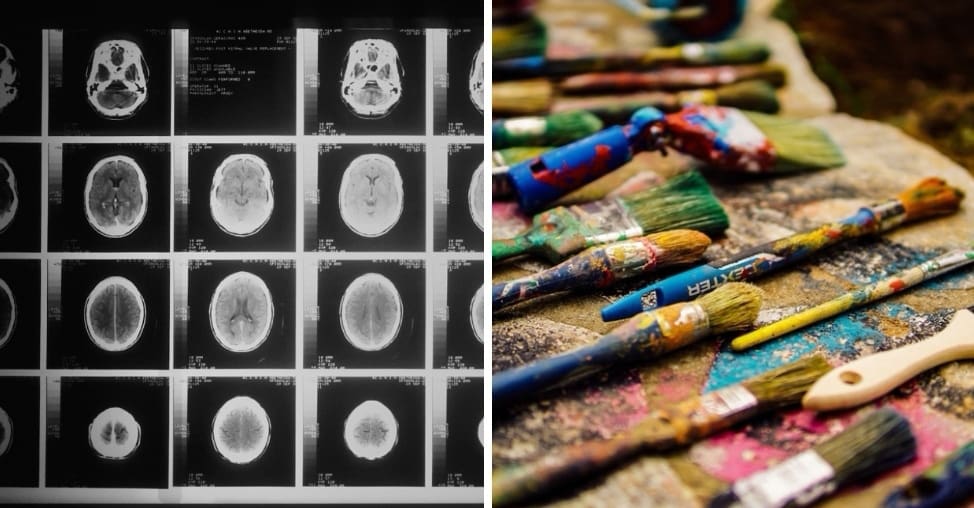

Mozog je veľmi zložitý, komplexný a jeden z najdôležitejších orgánov v ľudskom tele, preto akékoľvek jeho poškodenie, môže mať a aj máva hlboký dopad na zdravie jednotlivca. Poškodenie mozgu môže byť spôsobené celou radou rôznych patologických situácii, ako napríklad súčasť mnohých diagnóz, vrátane mŕtvice, traumatických poranení mozgu a nádorov mozgu.

Chiropraktik sa stal umelcom

V auguste 1989 dostal 35-ročný Jon Sarkin mozgovú príhodu a podstúpil operáciu, pri ktorej mu lekári museli odstrániť malú časť mozgu. Akonáhle sa Sarkin prebudil z narkózy mal priam nevysvetliteľné nutkanie začať kresliť, o čo nikdy predtým vo svojom živote nejavil záujem. Sarkin sa stal plodným a nadaným umelcom a jeho práce boli predstavené po celom svete.